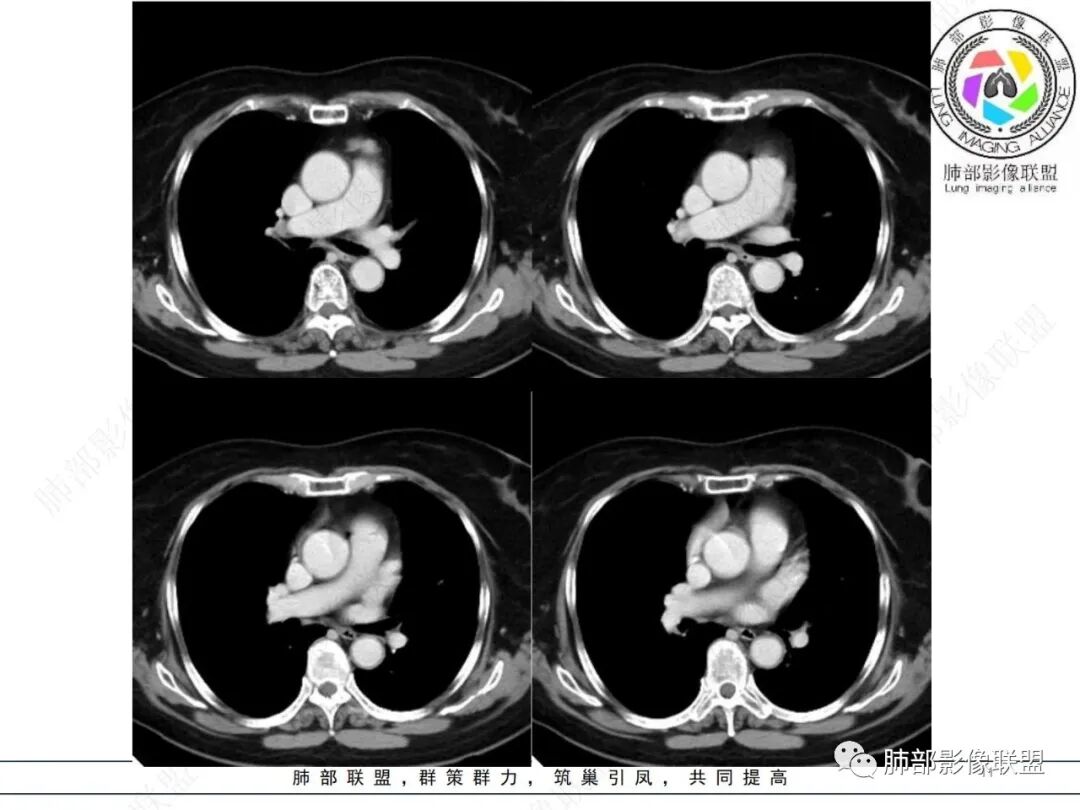

前上纵隔偏左侧实性病灶,边界清楚,边缘彭隆,浅分叶,内部密度均匀,未见钙化、脂肪密度,周围脂肪间隙清晰。

包膜完整,纤维分隔,结节感明显

平扫密度较均匀,增强渐进性不均匀强化,内见低密度纤维分隔。未见肿大淋巴结。未见胸腔积液。

肿块边界清楚,低密度纤维间隔,未见侵犯转移及增大淋巴结,多见于胸腺瘤AB型